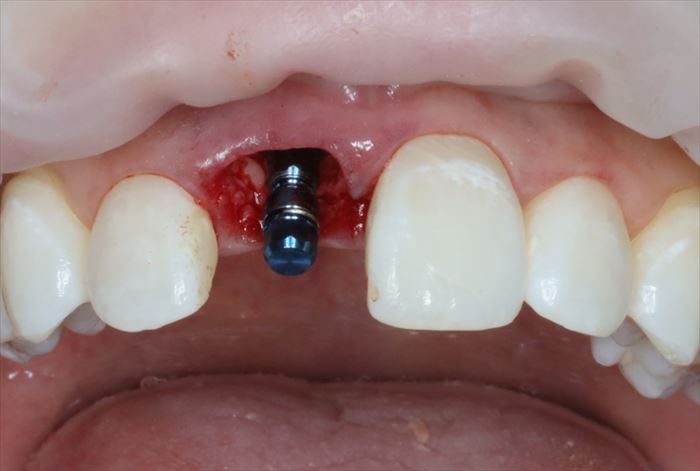

表面麻酔+注射による局所麻酔を行いスタートです。

まずは現状の仮歯が外れました。

_

続いて支台築造と周囲の歯質が取れました。

まだ歯根が残っていますが歯肉が入り込んでいたことが判ります。

残っていた歯根を抜歯し、顕微鏡下で抜歯窩内部の掻爬を終えました。

心配していた唇側の骨は無事に保存できました。

ここからはドリリングを行い、インプラントを植えるためのインプラント床(しょう)を形成します。

深度ゲージを挿入して角度・深さを確認している場面です。